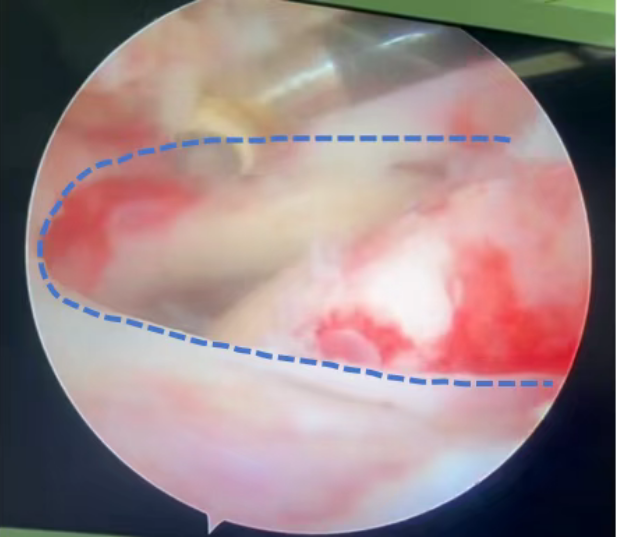

▲关节镜下见肩袖撕裂呈巨大“U”(蓝色虚线所示)